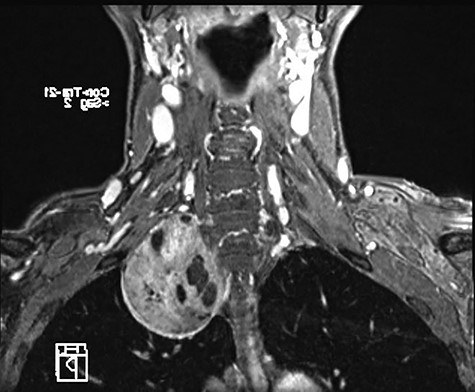

A 58-year-old female smoker with a history of cosmetic surgery complained of a large supraclavicular cervical mass associated with some neurological disorders (including anisocoria and ptosis of the right eyelid) since 2014. An ultrasound of the neck with cytological examination raised the suspicion of ‘Schwannoma’ with liquid content. Computed tomography (CT) of the neck and chest confirmed the presence of a 6.6 × 6 cm paracervical and paramediastinal right mass that dislocated the trachea and esophagus. The injury was also confirmed by nuclear magnetic resonance imaging (MRI) of the neck and chest (Figs 1, 2).

MRI showing paravertebral neurinoma with liquid content (C7-D3) with right intrathoracic involvement compressing the mediastinal structures without signs of vascular infiltration.